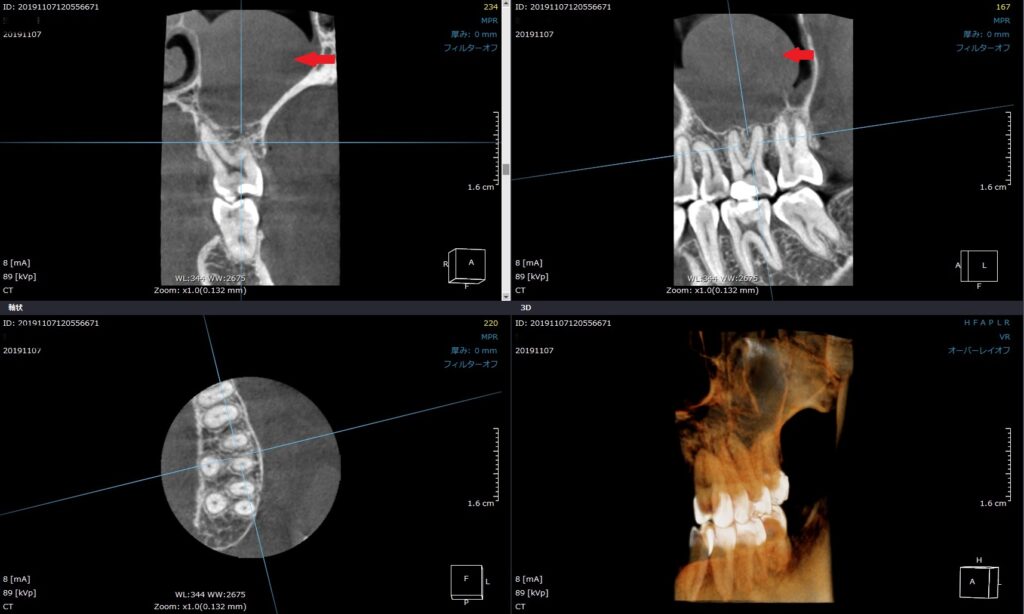

CTの写真です。

左上6番目の歯ですが、赤い矢印の部分が灰色に膨らんでいるのが分かりますでしょうか?

ここは上の奥歯の上に位置する「上顎洞(副鼻腔)」と呼ばれる、

蓄膿症になる鼻の空洞です。

こちらに膿がたまって炎症を起こしている状態です。

画像の上の歯、右から2番目には、白く詰め物があり、

2週間前に治療をしてもらった跡が見えます。